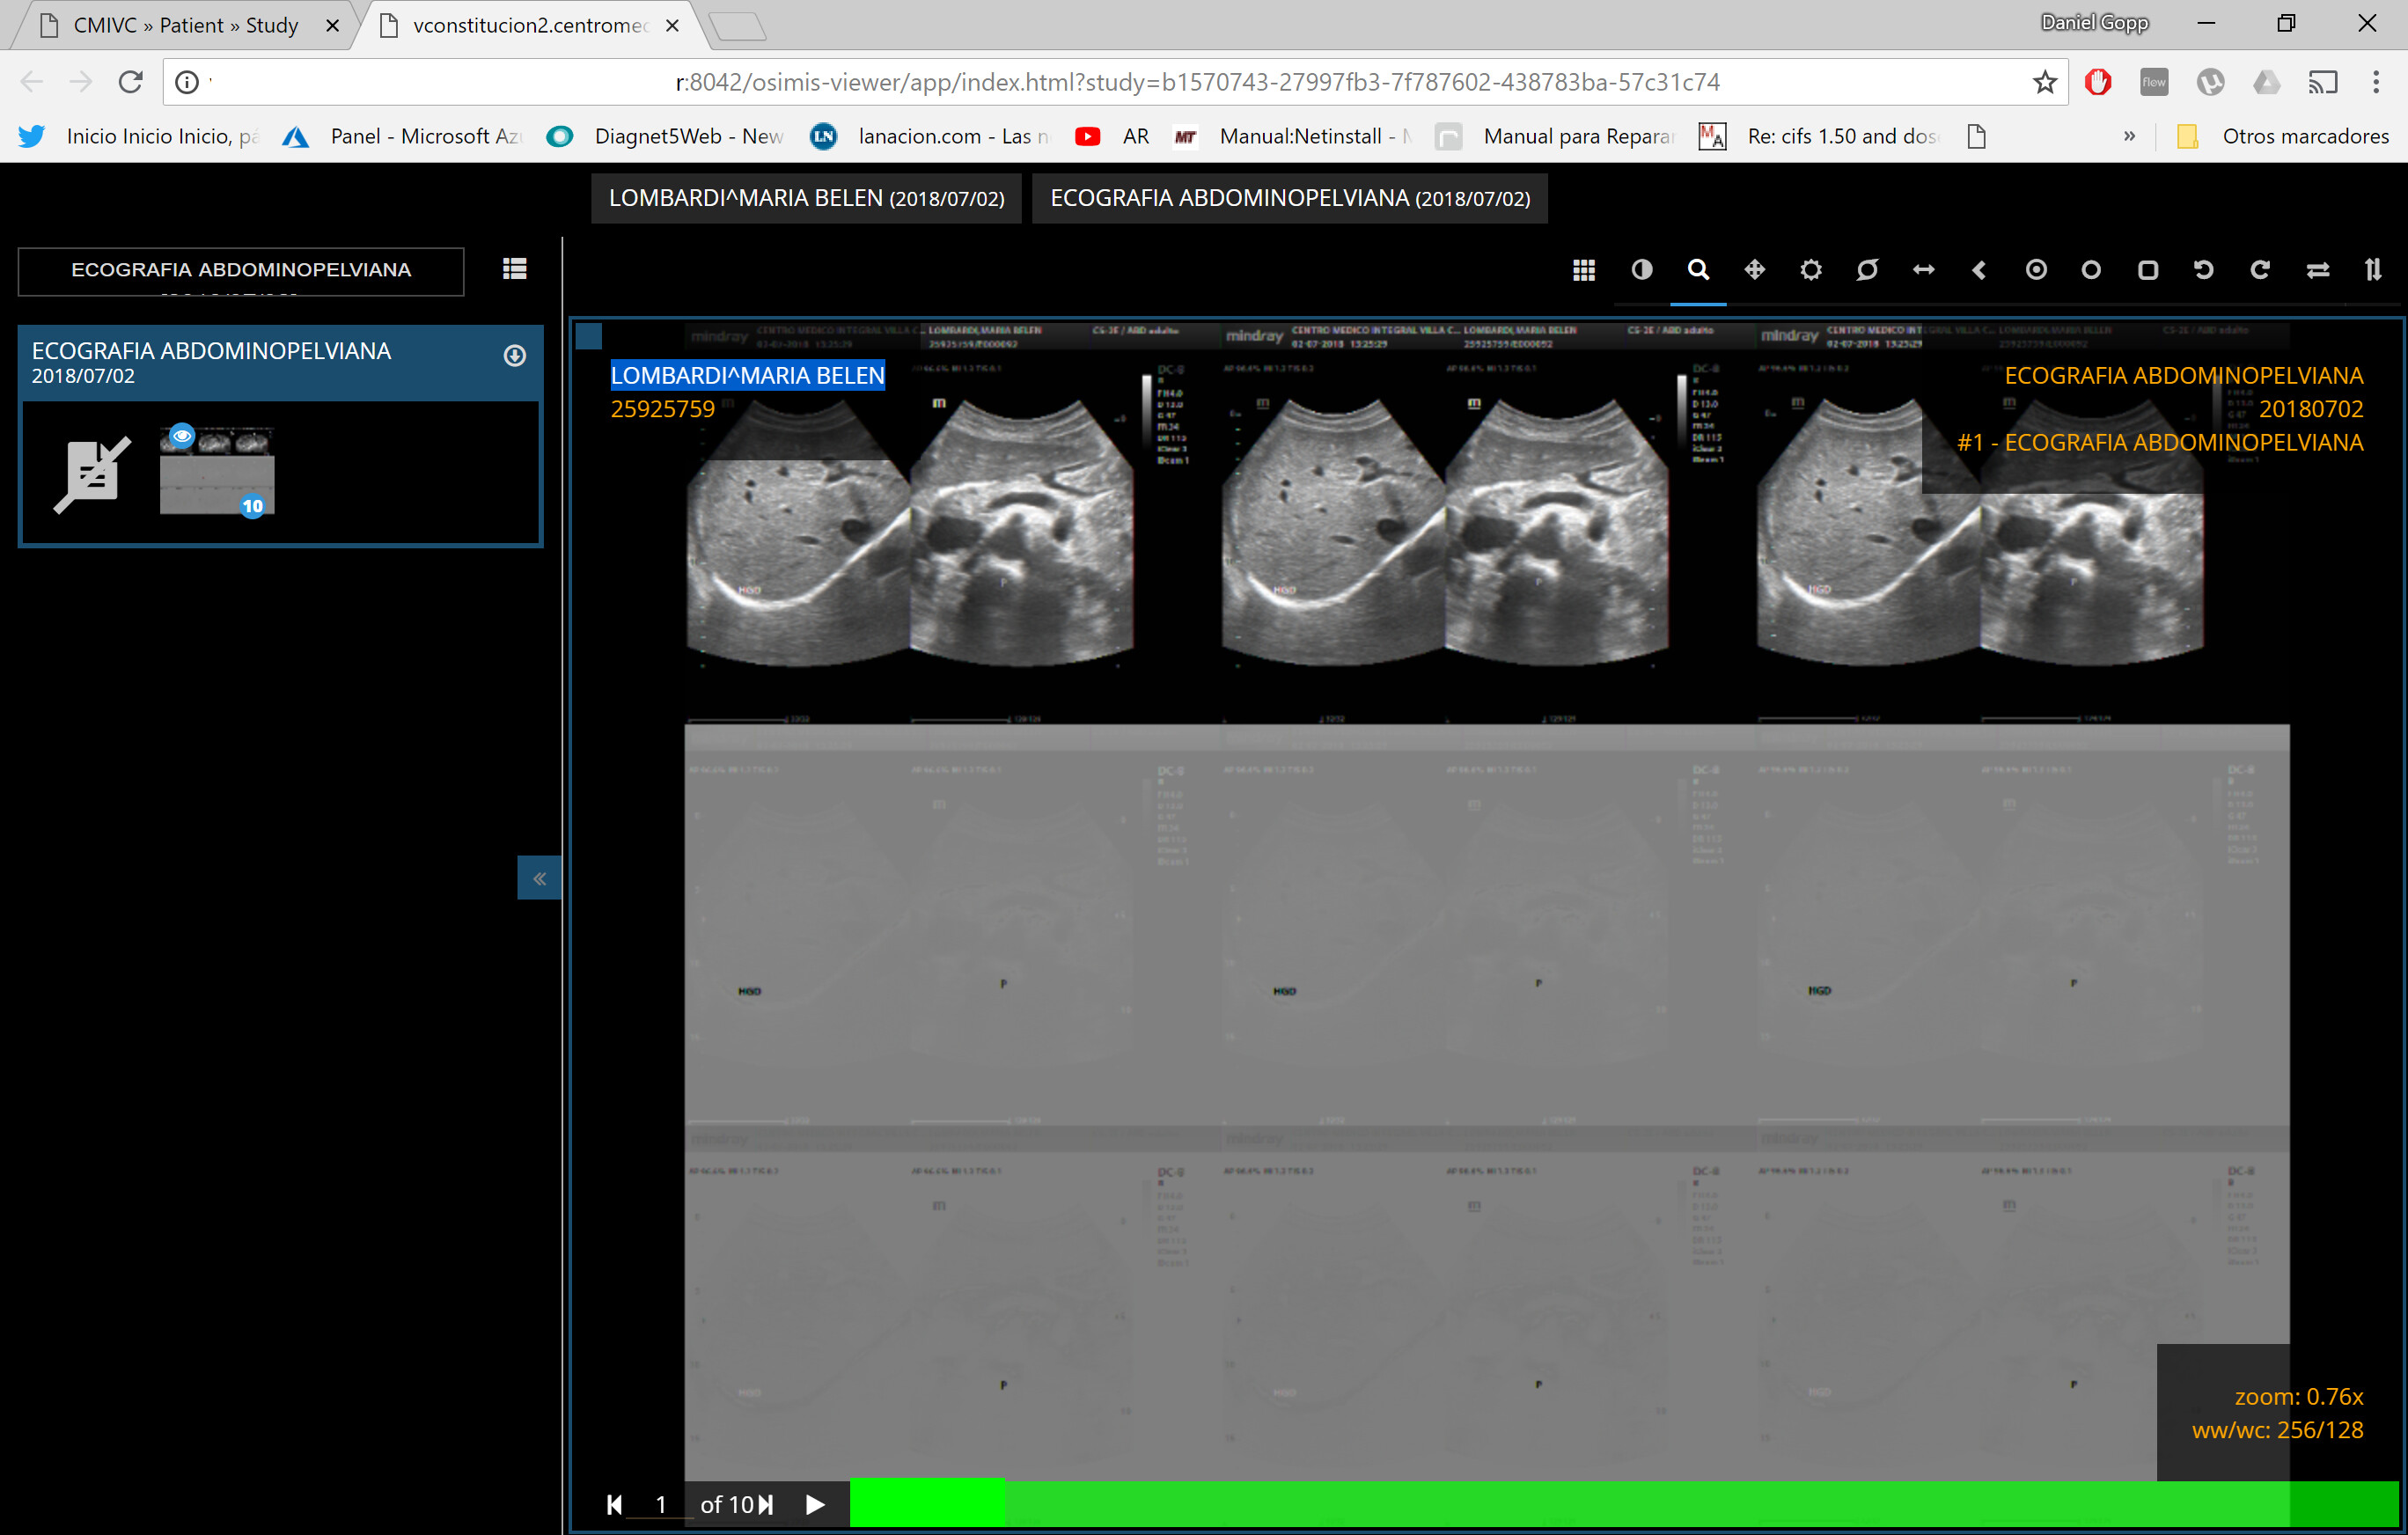

Hi. Retrieving an image in US mode, I can not see it correctly through the web viewer. I understand that the images in the US mode are encoded in another way. Is there any way of being able to view them in the web viewer correctly?

Hi. Thanks for your answer. I attach how i see it, and my configuration. There is no error on the log. Im using windows. If is possible, can you tell me how i can start the service with debug level log? Thanks (and sorry my english).